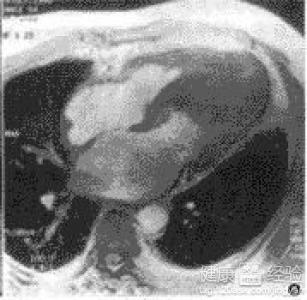

摘要:關于擴張性心肌病的最新治療,小巷深處的隱藏寶藏正逐漸為人們所發(fā)現(xiàn)。通過先進的醫(yī)療技術和方法,擴張性心肌病的治療取得了新的進展。這些治療方法旨在改善心臟功能,提高患者生活質量。小巷深處的醫(yī)療機構或專家可能隱藏著寶貴的治療經驗和方法,為尋求最佳治療方案的病患帶來希望。更多詳細信息需要進一步探索和研究。

擴張性心肌病是一種嚴重的心臟疾病,但“心之港灣”為你帶來希望,這里的專家團隊一直在深入研究擴張性心肌病的最新治療方法,并深知每位患者都渴望得到最佳的治療和關懷,他們努力不懈,為患者帶來生機和新生。

你將了解到最新的藥物治療、心臟康復計劃以及生活方式調整等方面的知識?!靶闹蹫场边€開展了一系列臨床試驗,為患者提供最新的治療方案,他們的治療方法全面且個性化,因為每個患者的狀況都是獨特的,所以需要因人而異定制治療方案。